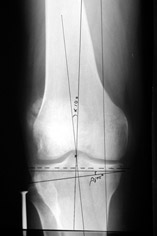

Отправитель: T. Derek V. Cooke 13 Сентябрь 2005, 23:51

|

Hello Alex:

Thanks for the clinical photo.

Your patient appears to have "Insquinting Knees"?

I am attaching a word doc with a 'print screen' of the program in use, showing the images being viewed and analysed

. On the right leg you can see some of the tools (from the tool bar above) applied to demonstrate a mild mech-axis varus of about 5 degrees.

On the left the bone landmarks used in the anlaysis are shown.

The data for the analysis are in the XLs sheet below, exported from the program automatically.

I have given a label of the abreviations and some normative values.

In essence she has a mild mech-axis varus of 7 degrees with some contribution from the femur (2) degrees and more from the tibia (6 degrees), none from the joint.

The analysis took about 6 mins.

Regards

Derek